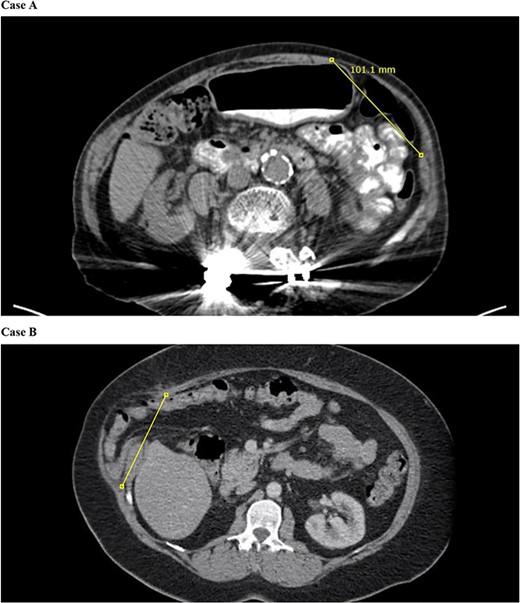

Computed tomography (CT) imaging of the abdomen and pelvis did not demonstrate clear evidence for an incisional hernia in the left flank region. CT imaging did show that her external oblique was intact; however, the internal oblique and transverse abdominis on the left side were detached from the linea semilunaris, resulting in an interparietal hernia (Fig. 1A).

CT of the abdomen and pelvis demonstrates separation of the transversus abdominis and internal abdominal oblique from the linea semilunaris.

CT imaging demonstrated a 13-cm flank hernia with the external oblique still intact; however, the internal oblique and transversus abdominis were detached from the linea semilunaris allowing herniation of non-dilated loops of bowel (Fig. 1B).